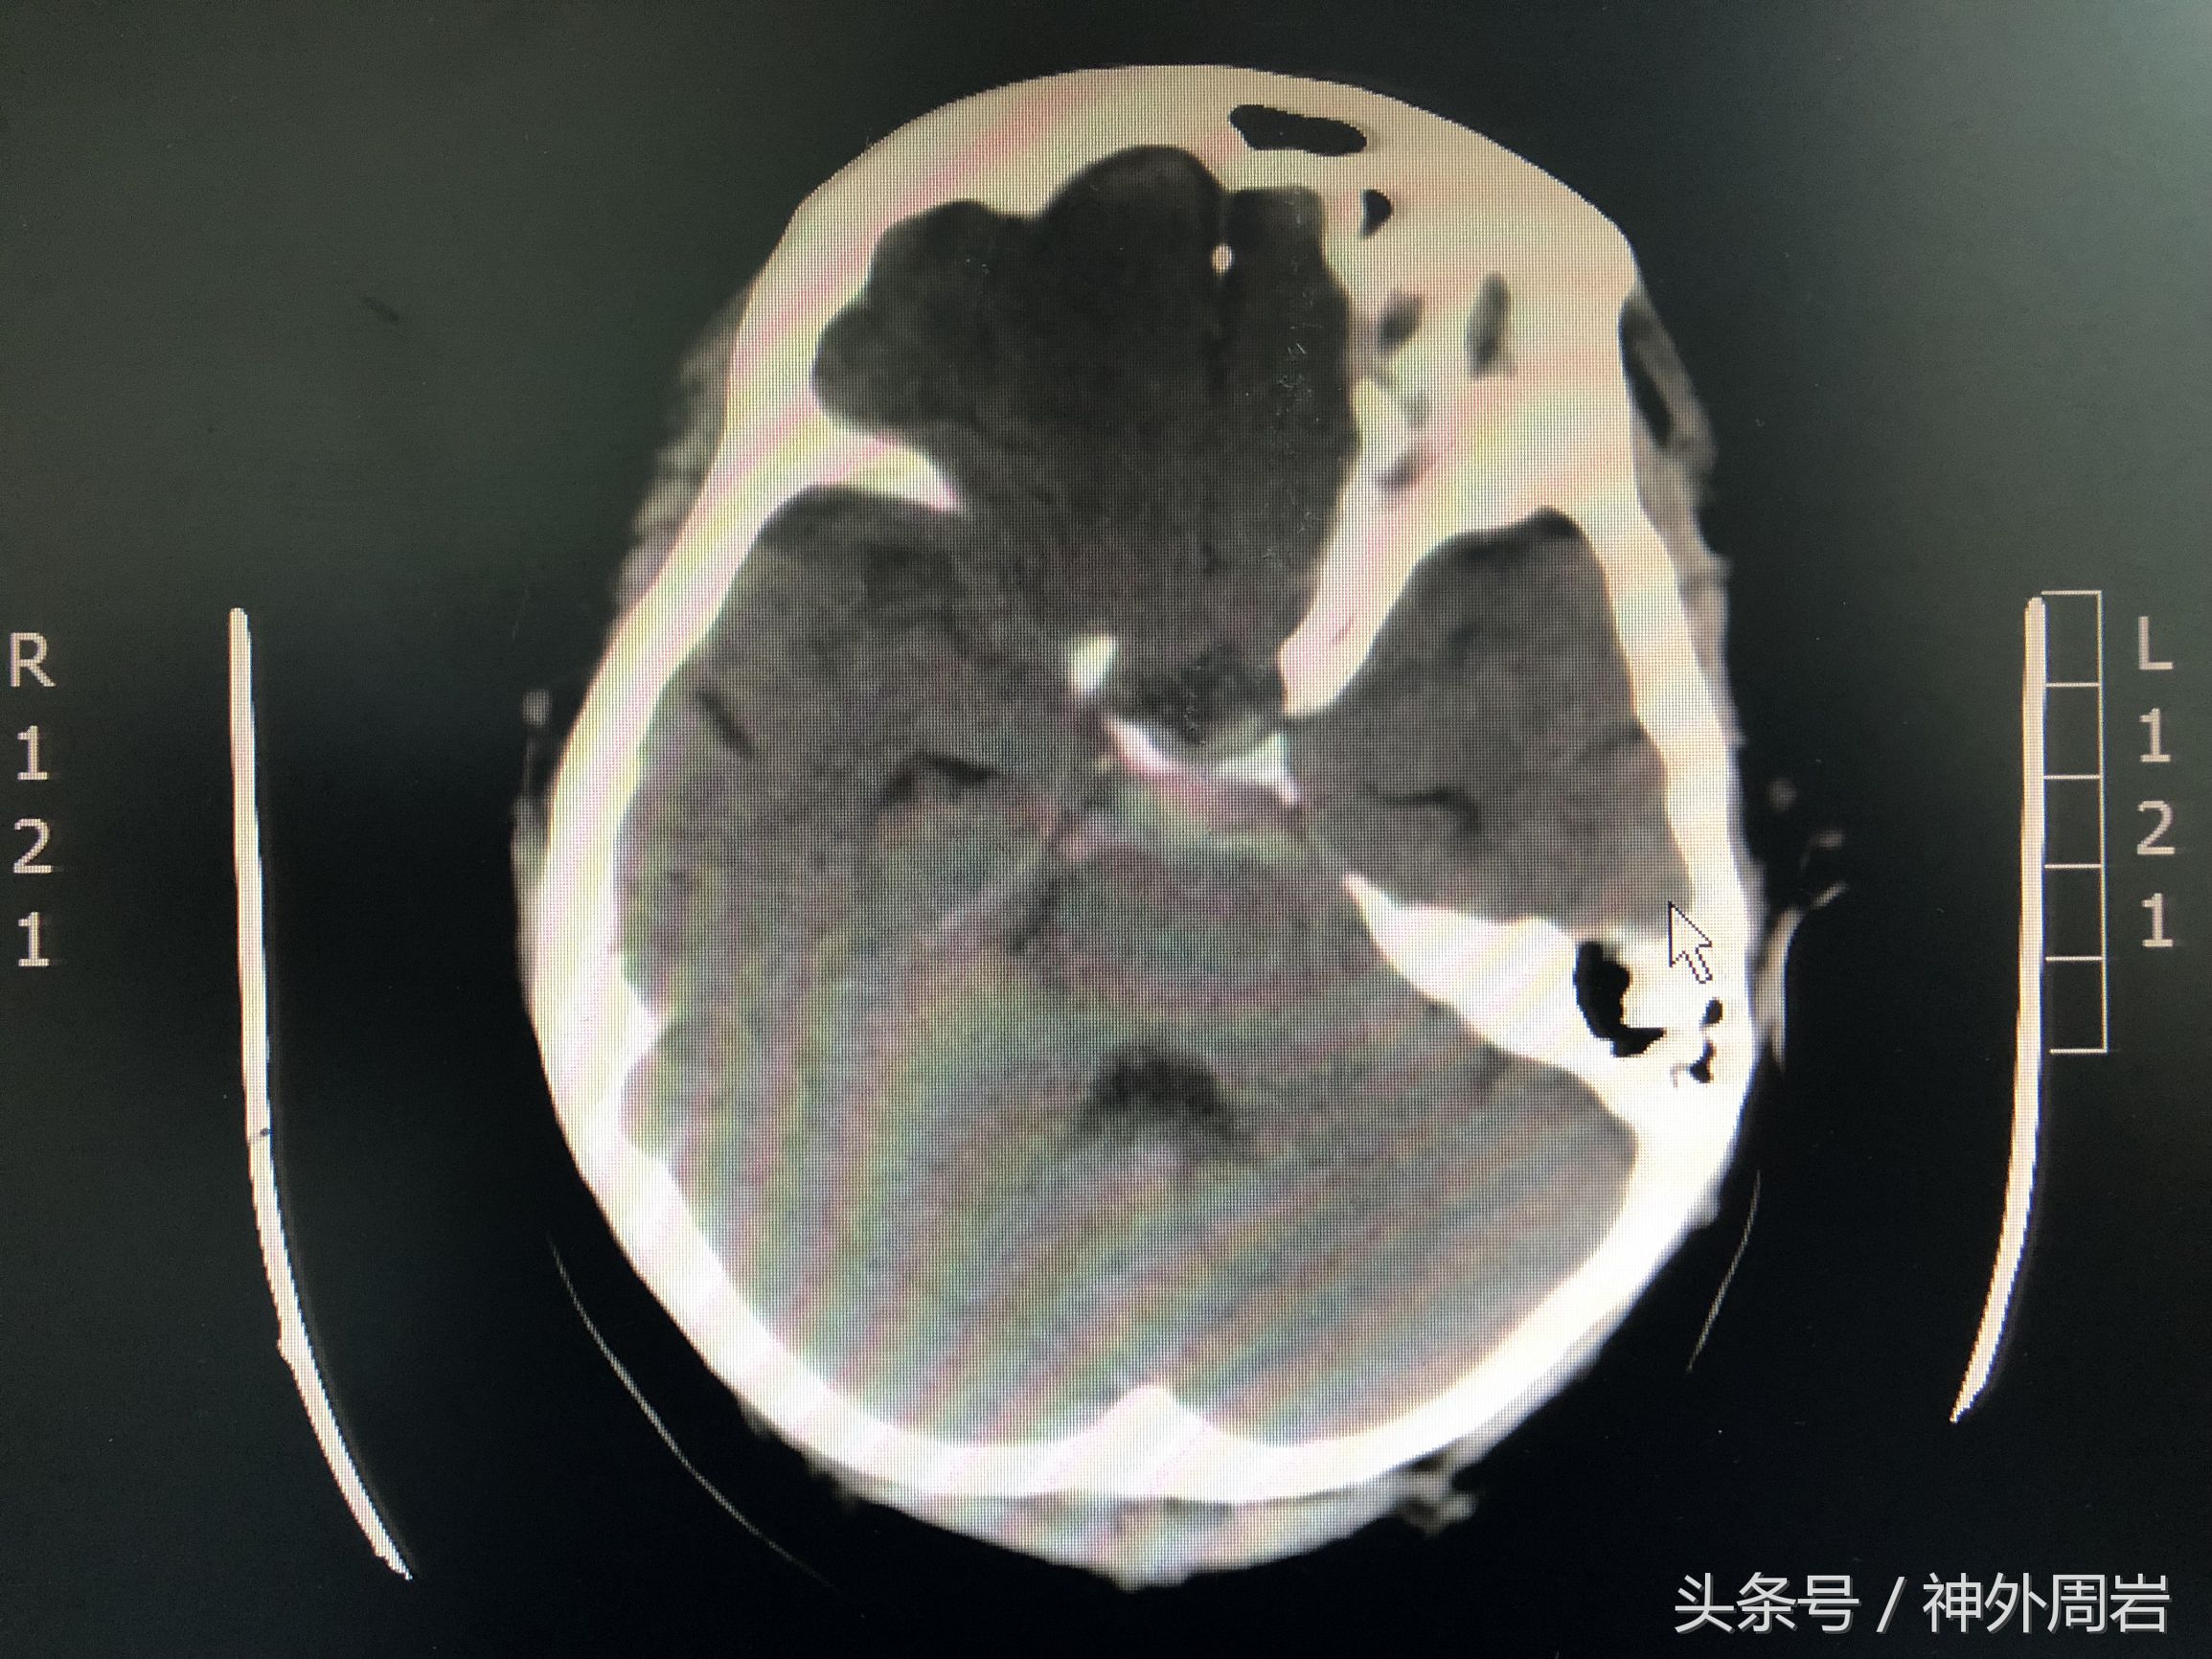

本文开头提到的病例就是典型的自发性蛛网膜下腔出血,“突发的剧烈头痛”是最常见的症状。30%妊娠期蛛网膜下腔出血可反应性引起血压升高、一过性蛋白尿,而40%致命性子痫同时并发自发性蛛网膜下腔出血。如怀疑蛛网膜下腔出血应首选CT,在放射吸收剂量<50mGY下不会增加胎儿畸形、生长受限和流产的几率。此外,怀疑存在脑血管疾病者还应积极行全脑血管造影检查。